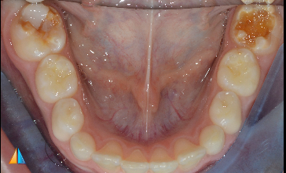

Severely hypomineralised lower molars